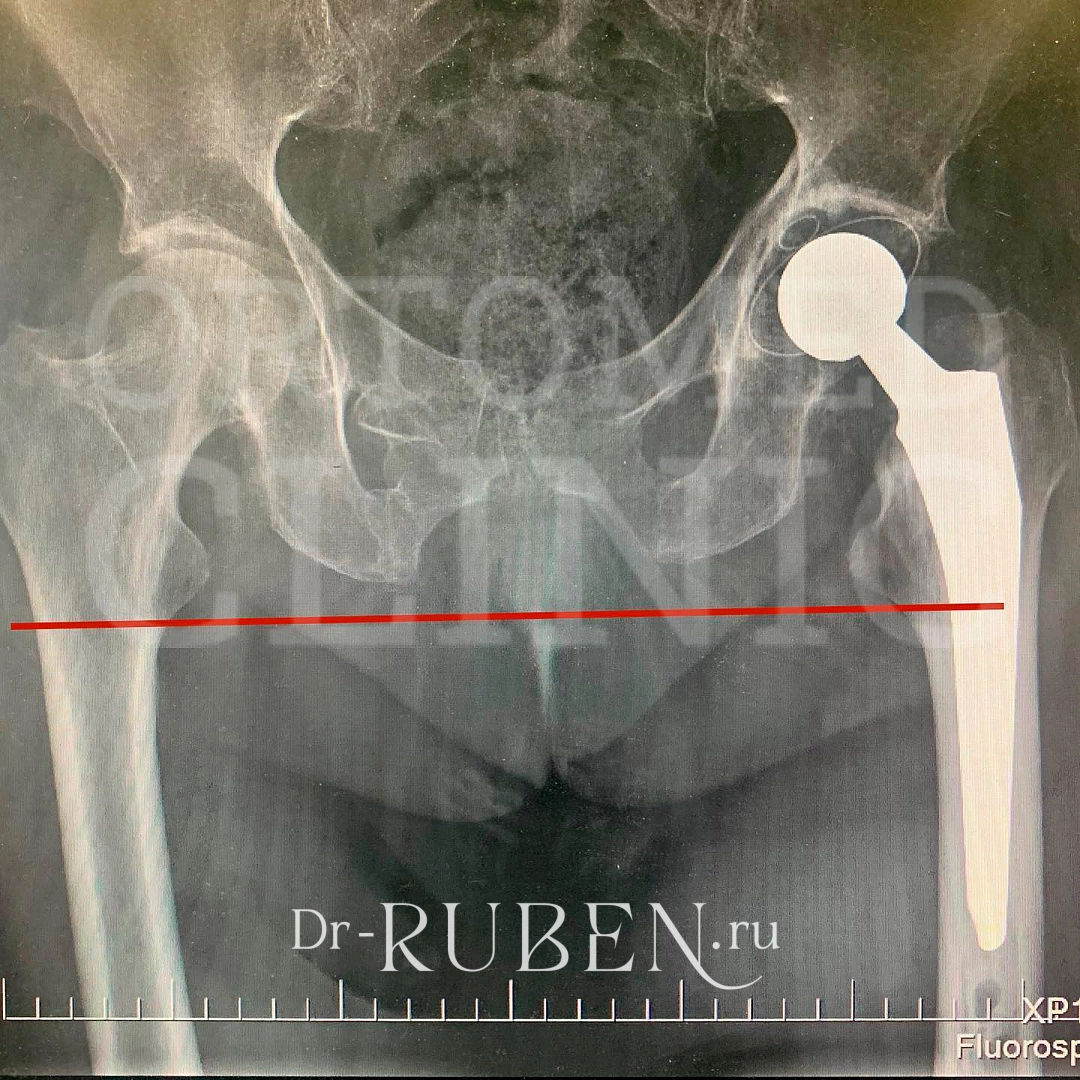

Иллюстрации и снимки, связанные с остеопенией шейки бедра

Раздел: Необычные решения